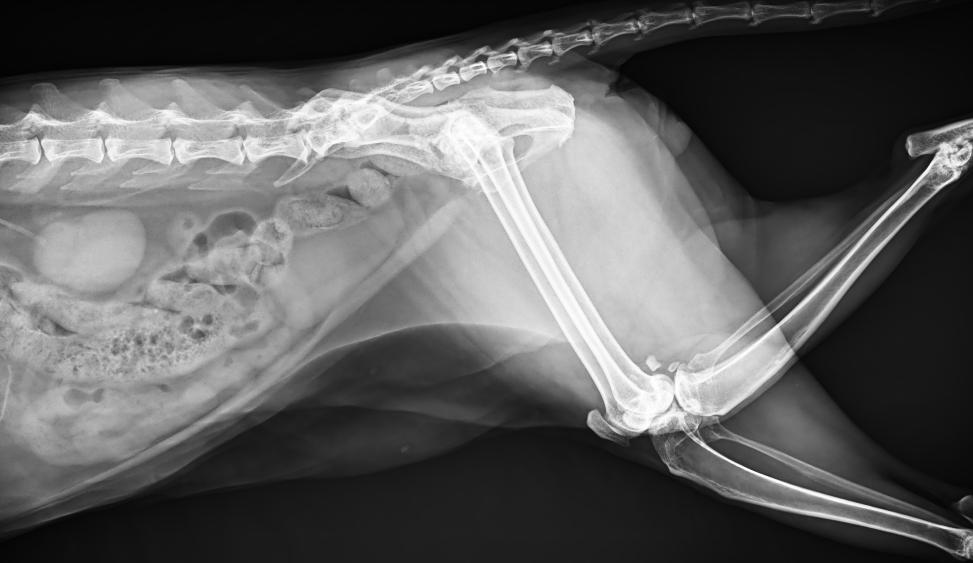

專為拍攝寵物設(shè)計(jì) VET1900 寵物DR

● 17*17大尺寸平板探測(cè)器,獲得高質(zhì)量圖像

● 優(yōu)異的空間分辨率及信噪比,提升圖像質(zhì)量

● 采用線噪聲消除技術(shù),使成像質(zhì)量提升40%

● 進(jìn)口高品質(zhì)球管,大功率、高熱容量、微焦點(diǎn),1.0/2.0mm雙焦點(diǎn)設(shè)計(jì)

● 25kHz高主逆變頻率,輸出電壓更穩(wěn)定;瞬時(shí)定格影像,無(wú)拖尾現(xiàn)象

● 智能高效的圖像處理軟件,大幅提升圖像質(zhì)量